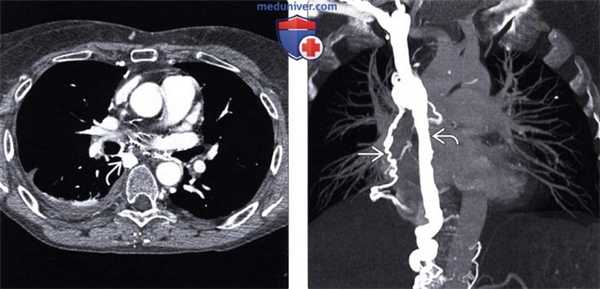

(Слева) На аксиальной КТ с контрастом, выполненной этому же пациенту, визуализируется самостоятельно сформировавшийся селезеночно-почечный шунт, а также расширенная левая почечная вена. Шунты, сформировавшиеся произвольно или при оперативном вмешательстве, способствуют снижению давления в венах пищевода, но в то же время приводят к повышению частоты развития энцефалопатии, а также венозного портального тромбоза, делая невозможным пересадку печени впоследствии или сильно затрудняя ее.

(Справа) Ангиограмма чревного ствола: контрастированные селезеночная вена и варикозно расширенные вены, однако признаков наличия кровотока в воротной вене не выявлено.

(Слева) На аксиальной КТ с контрастным усилением у пожилой женщины, предъявляющей жалобы на одутловатость лица, определяется обструкция верхней полой вены (ВПВ) с наличием коллатерального тока крови по расширенной непарной вене и другим венам в средостении.

(Справа) На корональной КТ с контрастным усилением у этой же пациентки визуализируется расширенная непарная вена и коллатеральные вены средостения, несущие кровь от органов, венозный отток от которых в норме осуществляется в систему ВПВ. При перераспределении крови она поступает в сердце по системе нижней полой вены (НПВ); несущие кровь из системы ВПВ сосуды иногда называют «нисходящими» коллатералями.